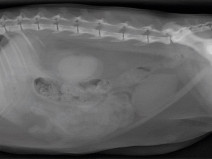

Le 4 mars 2017Aix-en-Provence (13100)Imagerie MédicaleG.E.I.M.199Après-midi Travaux pratiques de radiographie / TP2 l'abdomen

Le GEIM vous propose une séance de travaux pratiques de radiographies sur l'abdomen. Tous les aspects sont abordés sous la forme de TP de lecture de radiographies numériques sur station de travail Osirix sur Mac (3 vétérinaires maximum/ordinateur).